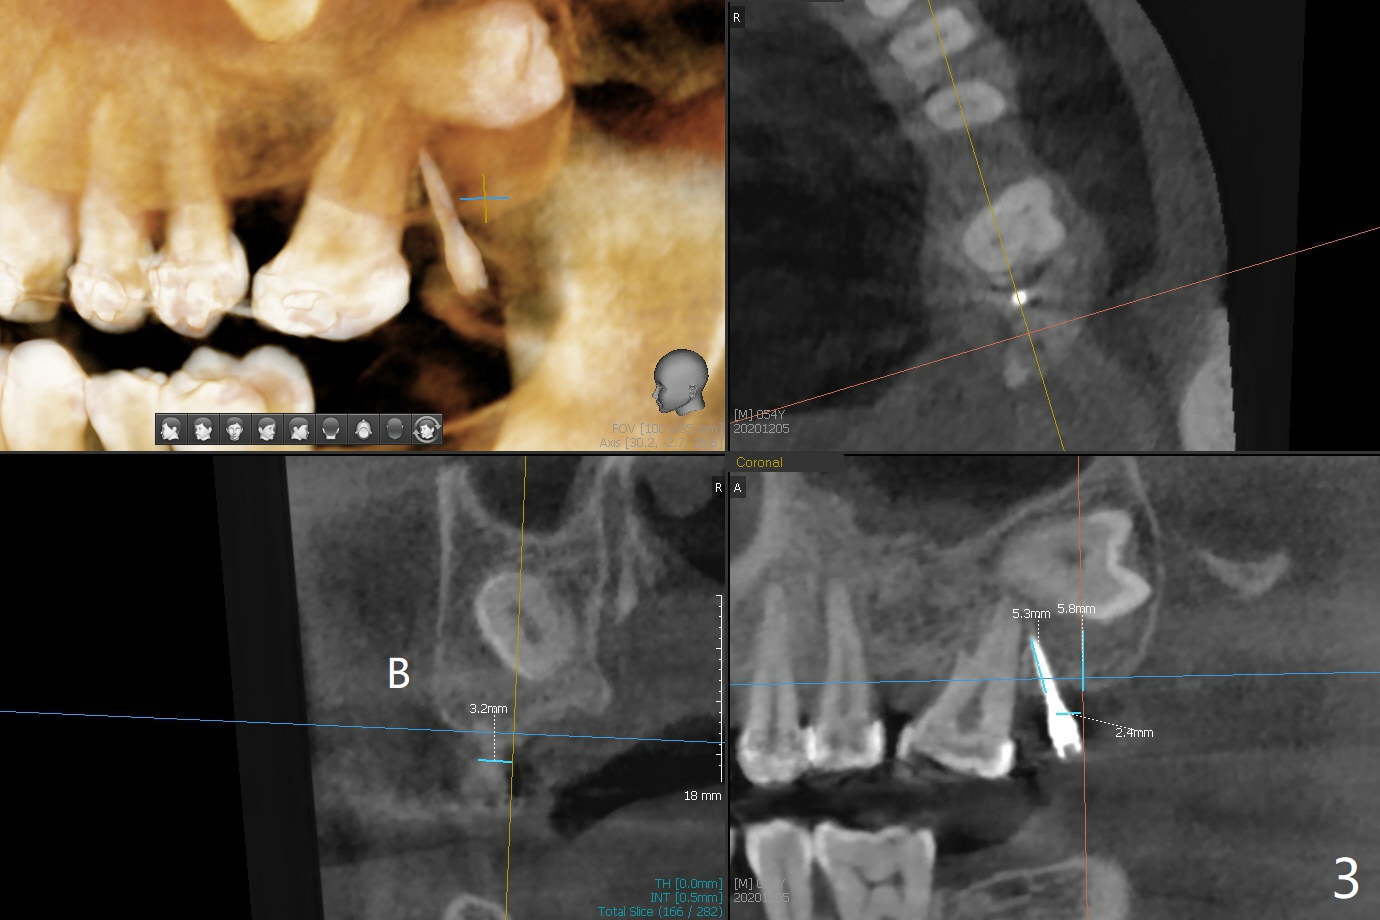

为了在左上6,左下7种植,使用右上3至左上5作为支抗推左上7远中,但是六个月效果不显著(图一),CT显示阻生牙(图一,二:8)没有阻挡。7远中植入1.6x8毫米微型植体,不过接近7根尖(图三),微型植体应该改变角度,而且往远中颊侧移位。最后效果不错(图四),植体马上启用(图五),而且同时取模做左下7导板。在微型植体牵引下,左上7的确往远中移位(图六,与图四对比),但是植体松动,马上植入3x10(2)毫米一段式植体,由于8阻挡,后者没有完全就位,稳定性差,没有启动。几天后也脱落。病人急着完成治疗,因为咀嚼困难。补救方法便是拔除阻生牙9(图七:x),让植体完全就位。切开后发现牙槽嵴处严重骨质吸收缺损(图八:D),离7很近,不适合种植。拔除8后(图九:S(socket)),两处植骨(粘性,图十),覆盖PRF膜,缝合。矫正九个月6空间相当双尖牙(图十二),还想增加2毫米才种植,病人急于完成治疗,所以再次植入微型植体,不同之处是切开,发现7远中颊侧骨质密度低(用探针),因此微型植体在腭侧植入(图十一:P),扭力似乎高,1.6x8毫米植体仿佛植入8牙槽窝(图十二:红虚线)。微型植体牵引一个月,磨牙缺牙间隙大约前磨牙大小,准备在远中(图十三)植入直径小植体(图十四),当后者整合时,用它继续推7。